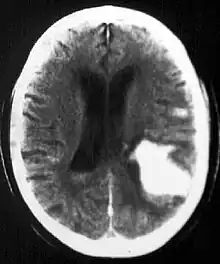

Multiple intraparenchymal hemorrhage

Intraparenchymal hemorrhage (IPH) is one form of intracerebral bleeding in which there is bleeding within brain parenchyma. The other form is intraventricular hemorrhage (IVH).[1]

Intraparenchymal hemorrhage accounts for approximately 8-13% of all strokes and results from a wide spectrum of disorders. It is more likely to result in death or major disability than ischemic stroke or subarachnoid hemorrhage, and therefore constitutes an immediate medical emergency. Intracerebral hemorrhages and accompanying edema may disrupt or compress adjacent brain tissue, leading to neurological dysfunction. Substantial displacement of brain parenchyma may cause elevation of intracranial pressure (ICP) and potentially fatal herniation syndromes.